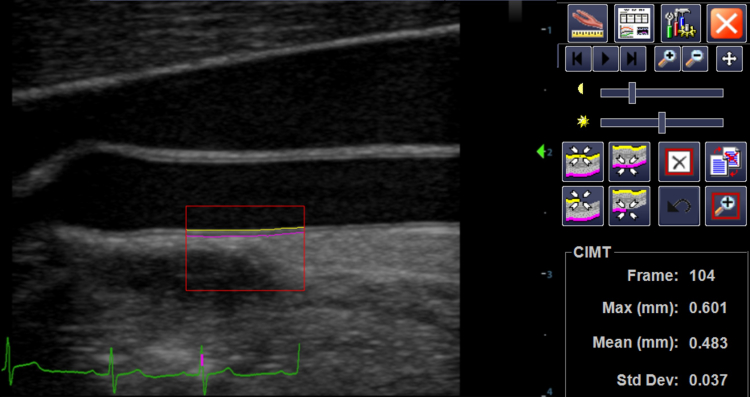

Below demonstrates measurement of far wall common carotid artery intima-media thickness.